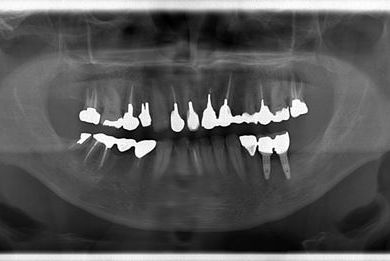

骨再生インプラント治療

性別/年齢 男性 / 53歳

主訴 インプラント治療相談。

治療方針 骨再生法にて、インプラント治療を可能にする。

治療内容 インプラント2本(GBR)、ハイブリッドセラミッククラウン2本

治療部位

5 6

総治療費 665,963円

治療期間 9ヶ月